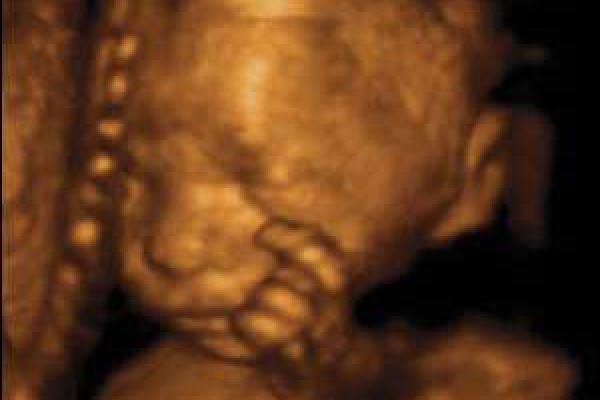

Il bambino ora prende quasi 200 grammi a settimana, pesa circa 1250 grammi e i suoi polmoni continuano ad esercitarsi nella respirazione. La testa cresce per fare spazio al cervello che ogni giorno vede nascere miliardi di nuovi neuroni, scalcia a più non posso ed è possibile contare i suoi movimenti per verificare il suo benessere e controllare che sia ben ossigenato. Per farlo, mettiti sdraiata su un fianco ogni giorno alla stessa ora, rilassati e concentrati su di lui, poi conta quanto tempo occorre al tuo piccolo per farsi sentire almeno dieci volte, conterai calci, pugni, singhiozzi e anche movimenti della testa e del sederino. La buona regola è che non servano più di due ore per arrivare a dieci.

Il bambino continua a crescere e ormai occupa quasi interamente lo spazio nell’utero.È possibile avvertire movimenti netti e precisi, al punto che potresti distinguere bene di quale parte del corpo si tratta, se la testa, il sederino o anche la schiena.

Il bambino è arrivato a circa 1400 grammi, è più cicciottello e la sua pelle è più liscia e rosea.Con le sue continue capriole, potrebbe trovare la posizione definitiva per la nascita.

Ora il piccolo pesa circa 1600 grammi, ogni giorno che passa mette su il grasso sottocutaneo e la pelle è meno rugosa, lo spazio disponibile è poco e i suoi movimenti sono meno “tellurici”.

L’utero è arrivato a circa 12 centimetri sopra la linea ombelicale trasversa e il piccolo pesa circa 1800 grammi ed è lungo circa 40 centimetri.

La peluria che lo ricopre comincia a scomparire mentre la vernice caseosa lo ricopre totalmente. Gli occhi distinguono la luce dal buio e, soprattutto, distingue il caldo dal freddo, al punto tale che si muove se viene posta una fonte di calore vicino alla pancia.